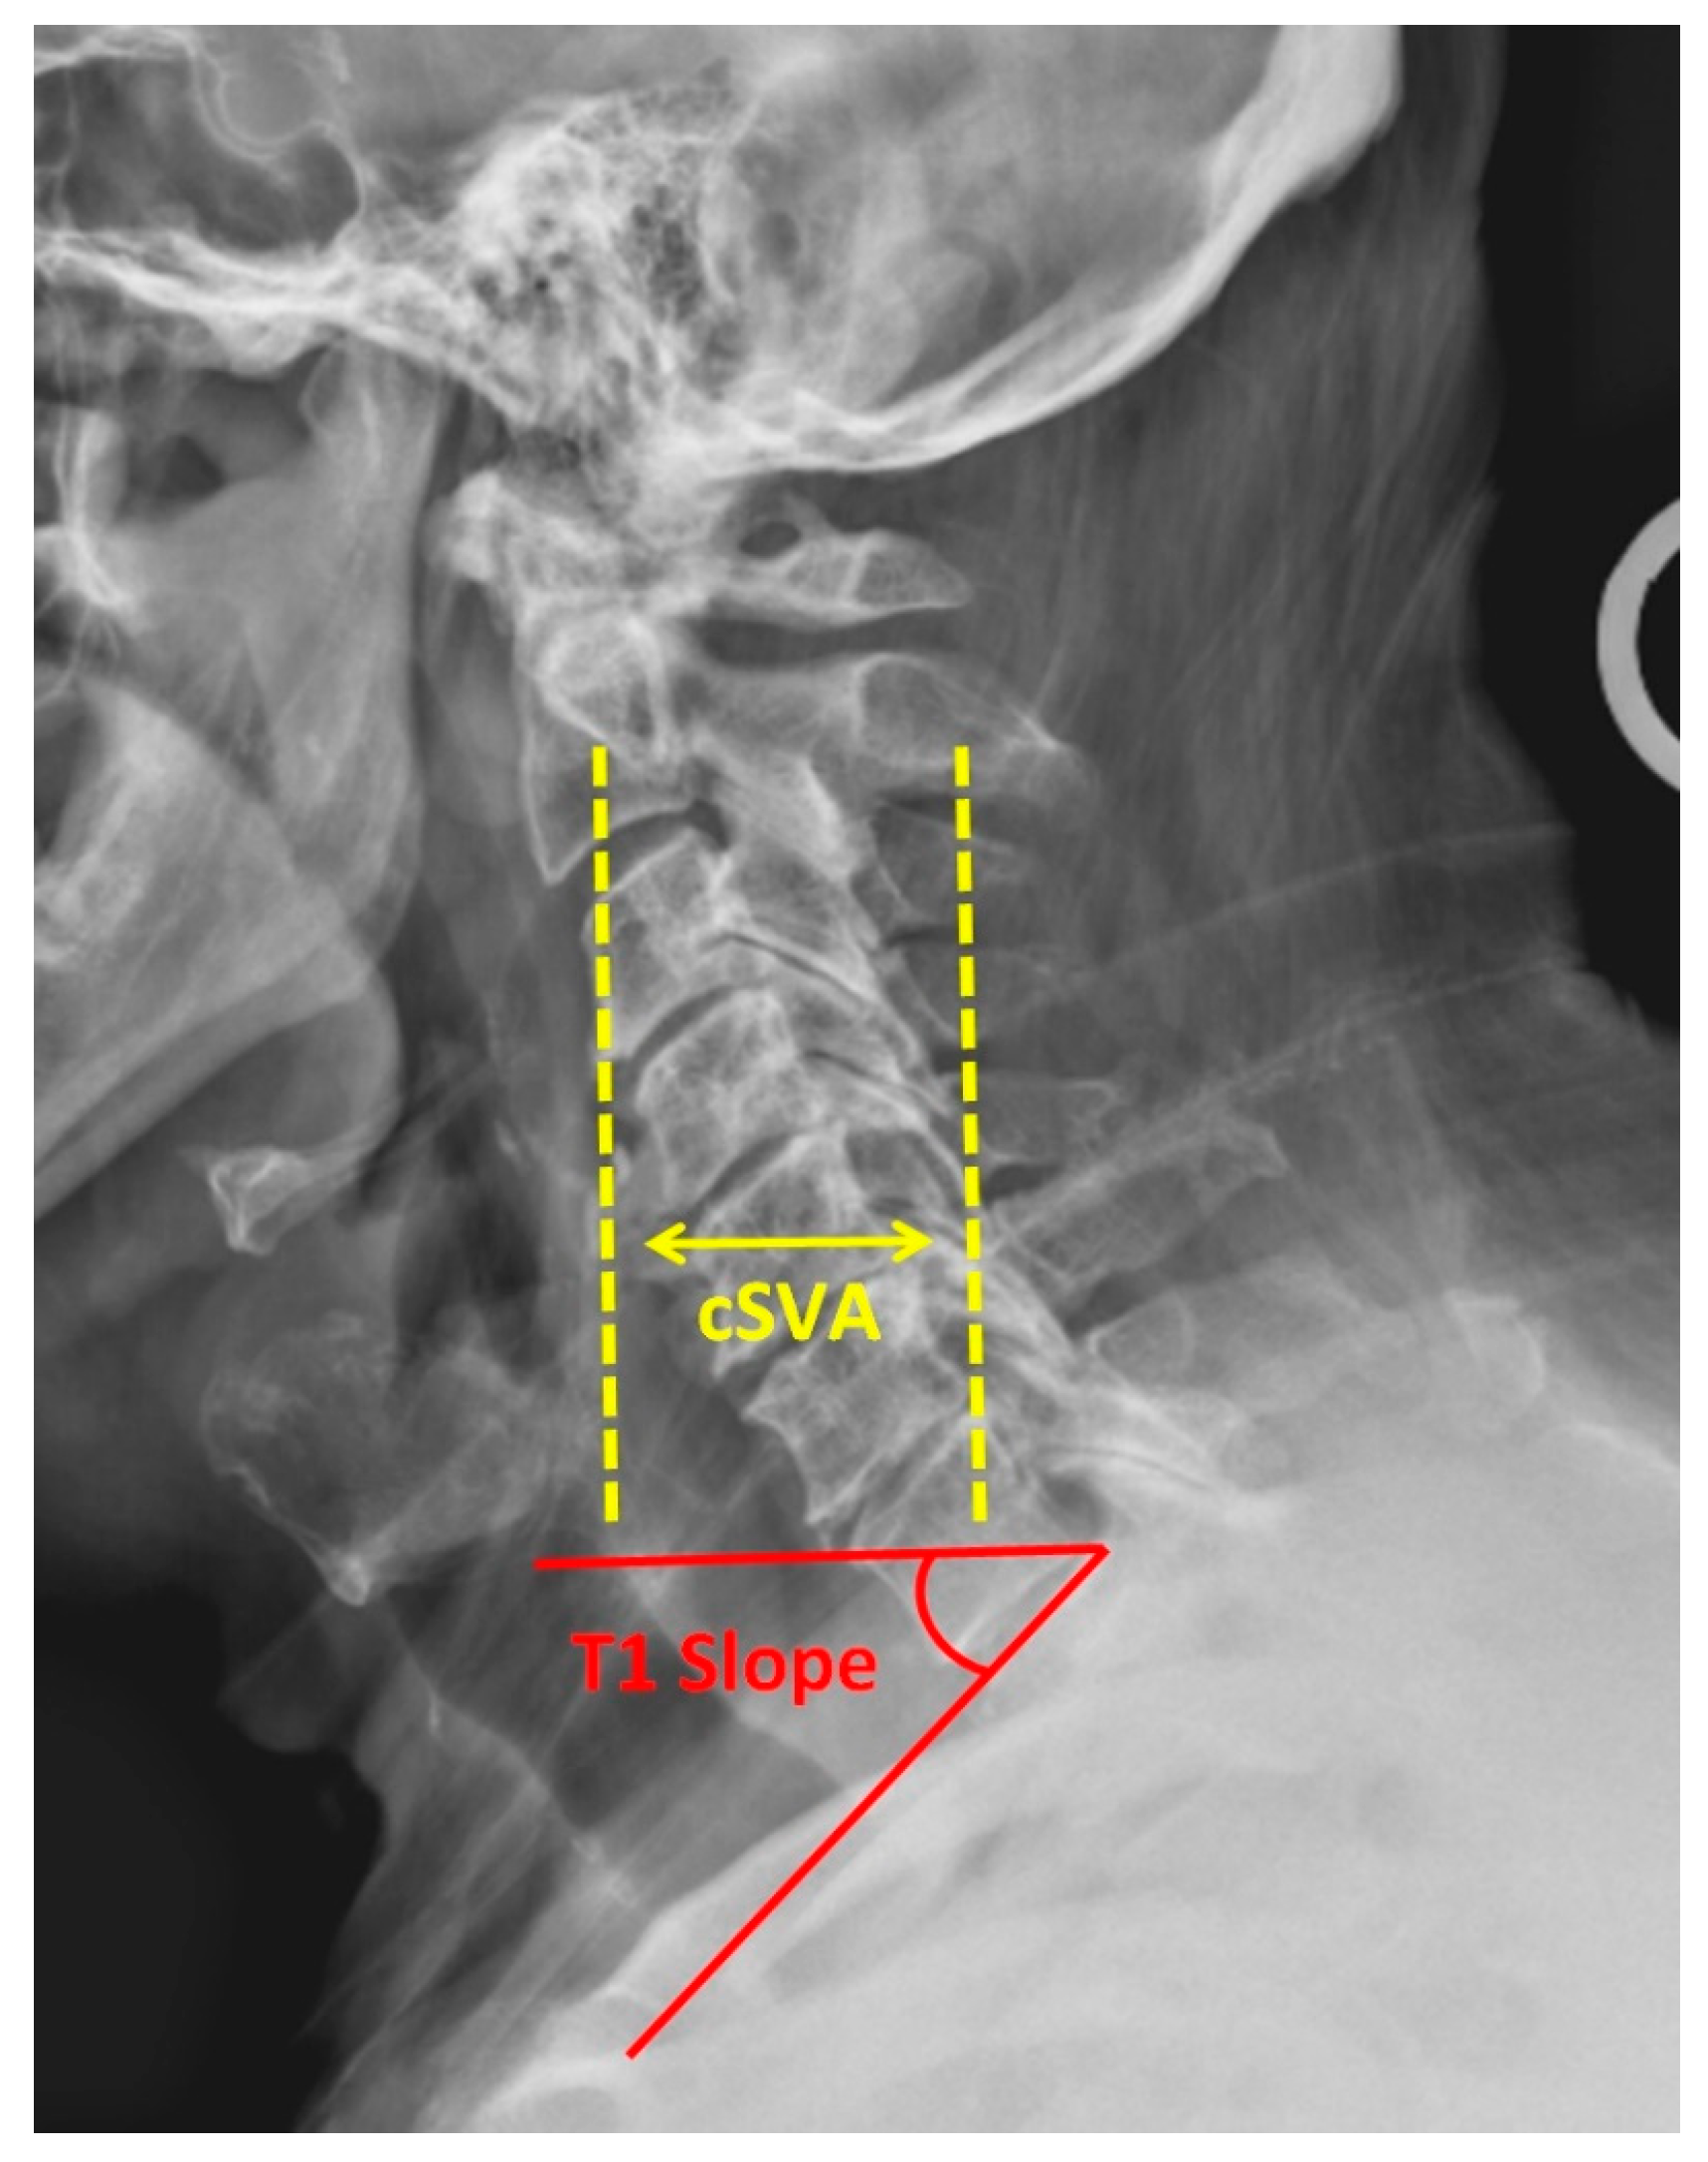

4. Sagittal Parameters

- Virk, S.; Lafage, R.; Elysee, J.; Louie, P.; Kim, H.J.; Albert, T.; Lenke, L.G.; Schwab, F.; Lafage, V. The 3 Sagittal Morphotypes That Define the Normal Cervical Spine: A Systematic Review of the Literature and an Analysis of Asymptomatic Volunteers. J. Bone Jt. Surg. Am. 2020, 102, e109. [Google Scholar] [CrossRef]

- Ling, F.P.; Chevillotte, T.; Leglise, A.; Thompson, W.; Bouthors, C.; Le Huec, J.C. Which parameters are relevant in sagittal balance analysis of the cervical spine? A literature review. Eur. Spine J. 2018, 27, 8–15. [Google Scholar] [CrossRef]

- Azimi, P.; Yazdanian, T.; Benzel, E.C.; Hai, Y.; Montazeri, A. Sagittal balance of the cervical spine: A systematic review and meta-analysis. Eur. Spine J. 2021, 30, 1411–1439. [Google Scholar] [CrossRef]